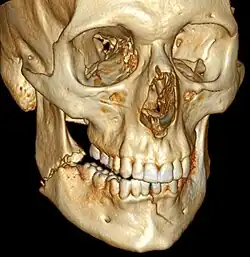

3D computed tomographic image of a mandible fracture in two places. One is a displaced right angle fracture and the other is a left parasymphyseal fracture.

Computed tomography is the most sensitive and specific of the imaging techniques. The facial bones can be visualized as slices through the skeletal in either the axial, coronal or sagittal planes. Images can be reconstructed into a 3-dimensional view, to give a better sense of the displacement of various fragments. 3D reconstruction, however, can mask smaller fractures owing to volume averaging, scatter artifact and surrounding structures simply blocking the view of underlying areas.